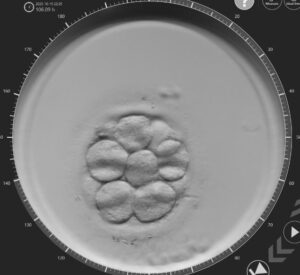

Hasta hace poco tiempo, luego de una FIV los embriólogos evaluaban de rutina la calidad [...]